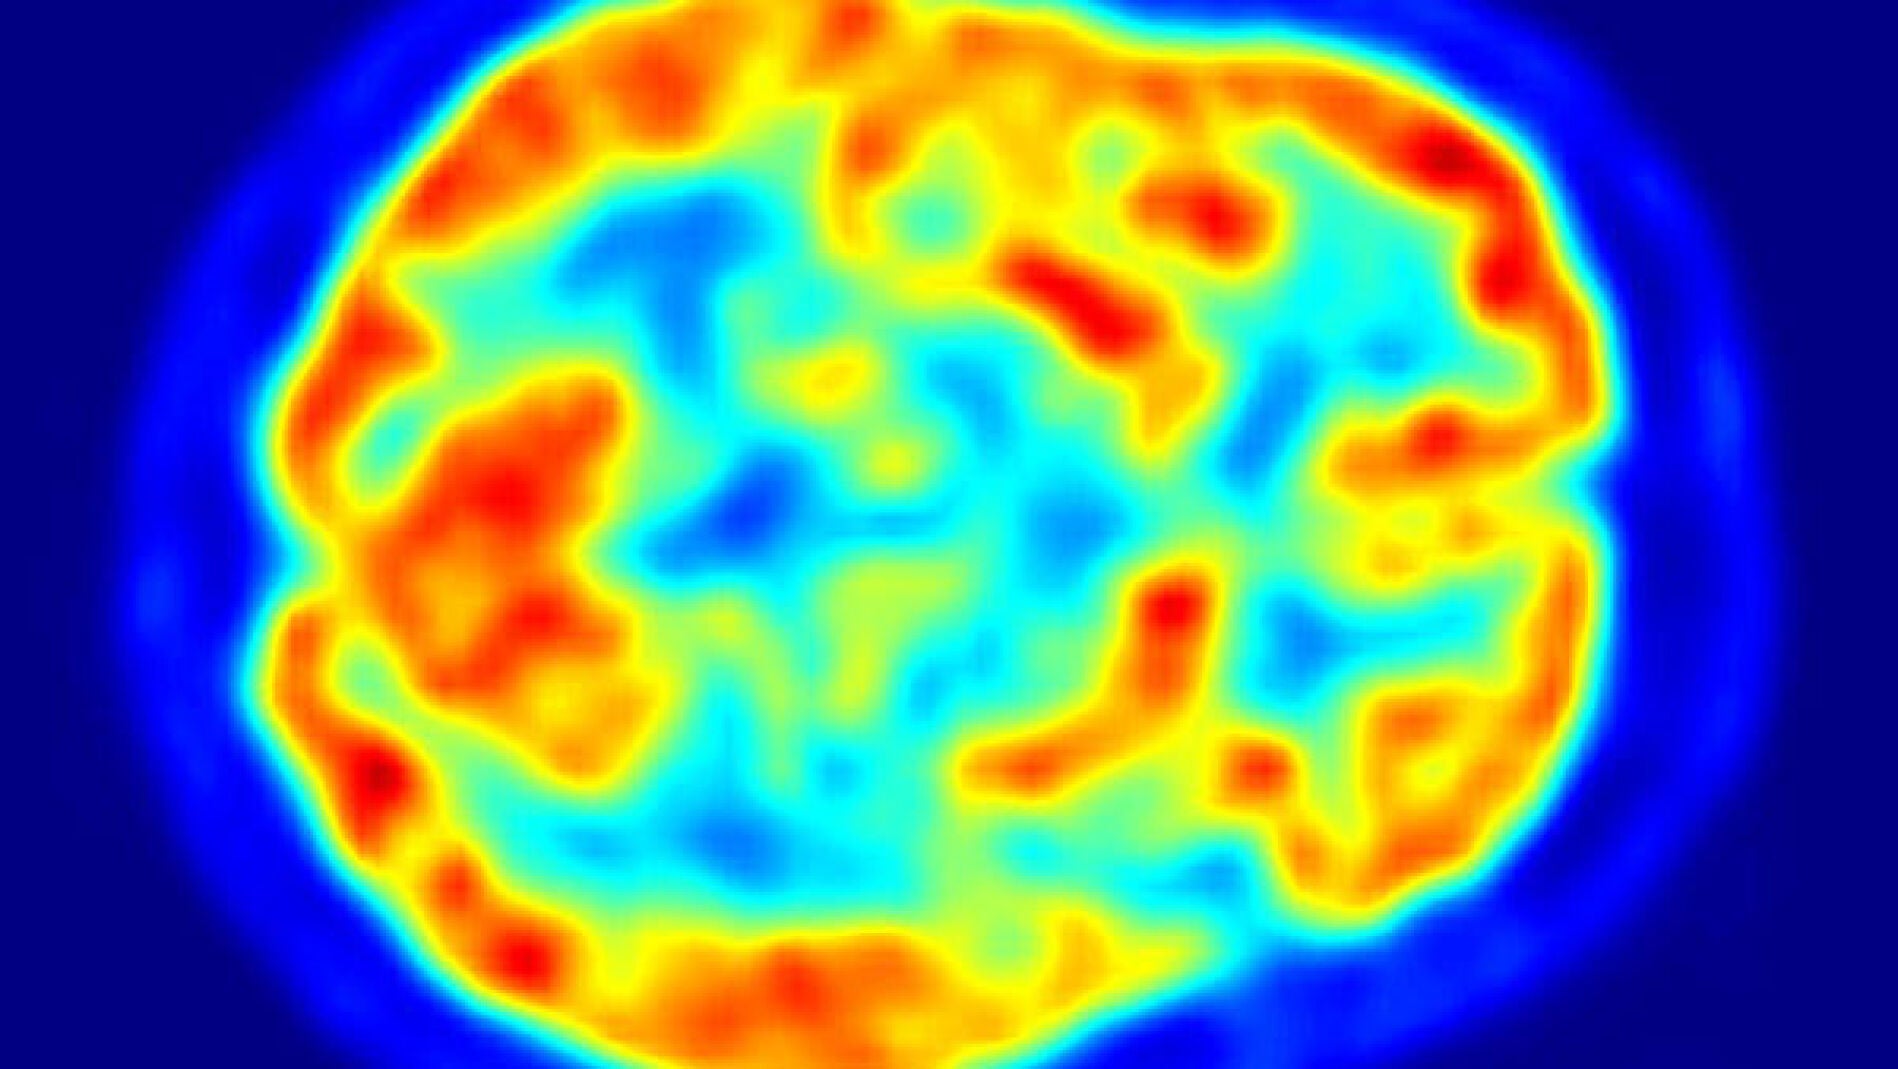

La forma del cerebro influye en la actividad cerebral de los seres humanos

Los patrones distintivos de la función cerebral que se producen cuando los seres humanos están en reposo están vinculados a la estructura física de sus cerebros, según un estudio publicado hoy por una universidad australiana.

El complejo trabajo matemático para analizar los datos cerebrales demostró que "la actividad del cerebro resuena dentro de las estructuras anatómicas precisas del mismo para producir las oscilaciones que observamos en estado de reposo", acotó Pearson.

En el estudio, los investigadores se valieron de los datos recogidos a través de las imágenes de resonanciamagnética (MRI) y de imágenes por resonancia magnética con tensores de difusión (DTI) para construir mapas tridimensionales de las estructuras de los cerebros de diez personas.

El MRI dio información sobre la estructura de la corteza cerebral y el DTI proporcionó un mapa anatómico de las conexiones subyacentes de la materia blanca en el cerebro, de acuerdo a este estudio publicado en la revista científica "Nature Communications".

El equipo multidisciplinario de científicos analizó los mapas cerebrales apoyándose en los estudios de las ondas armónicas, que describen las vibraciones naturales de un sistema en el que todas las partes se mueven juntas con la misma frecuencia.